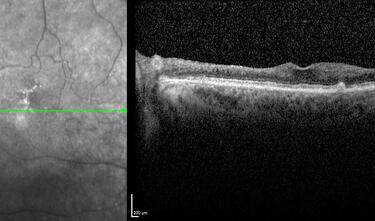

Clase 1 - Conceptos esenciales en fisiología y anatomía de la retina

Clase 20 - Signos clave en patología traccional vítrorretiniana

Clase 21 - Desprendimiento de vítreo y desprendimiento de retina